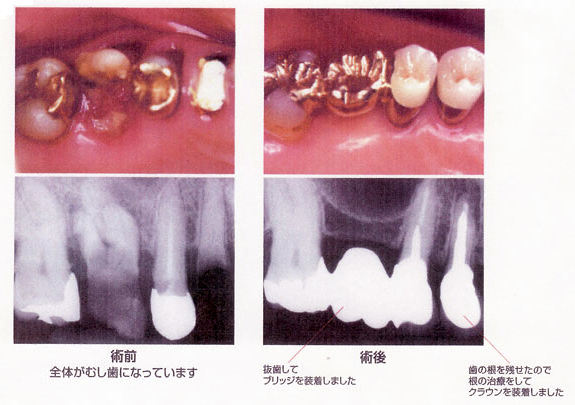

CASE 04 すでに神経を失った歯のむし歯

【病態】

【治療(過程)】